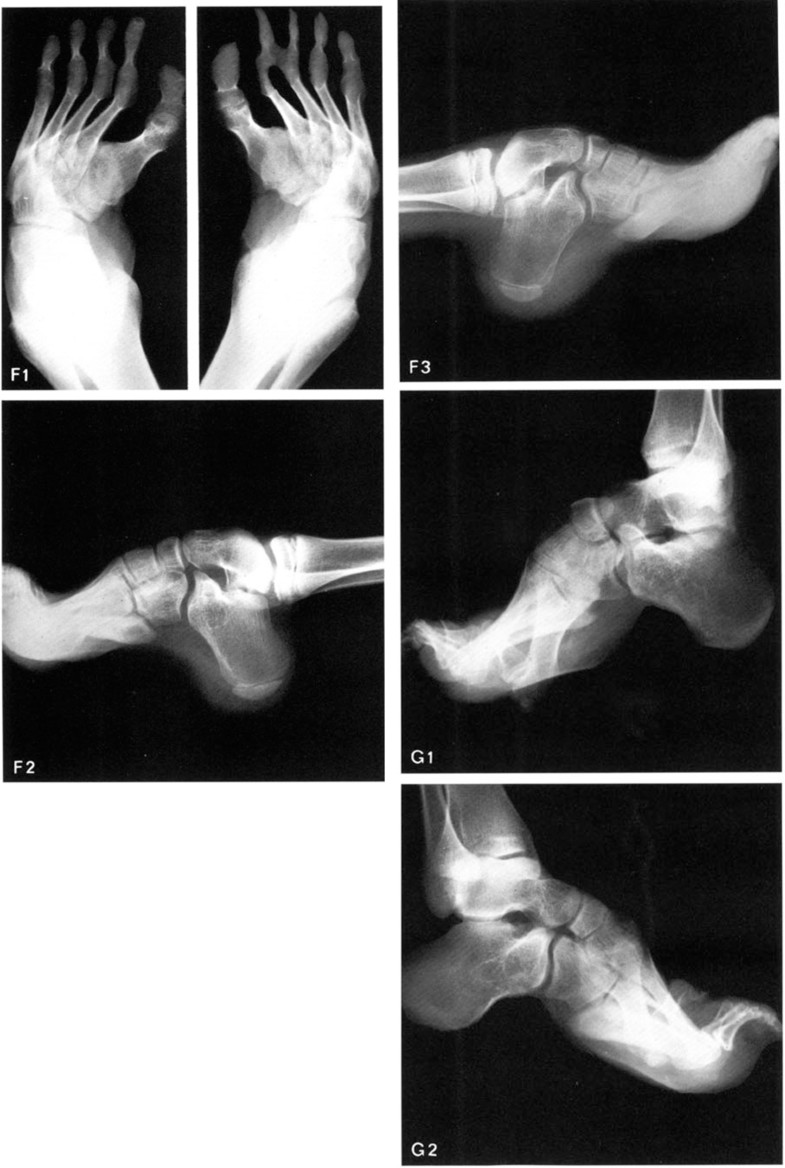

Pes Cavus L? G?. Symptoms predominantly include a high arch of the foot resulting in pain and possible fractures pes cavus is characterized by a high arch that places stress on both the ball of the foot and the heel of the foot. This deformity does not flatten on weight bearing.

Treatment of cavus due to muscle imbalance. Common complaints associated with pes cavus include pain under the metatarsal heads and the heel, lateral ankle sprains, and footwear issues. The feet don't lie flat properly, with the effect of undue forces in the wrong places causing bone or tissue damage. Pes cavus is a multiplanar foot deformity characterised by an abnormally high medial longitudinal arch.